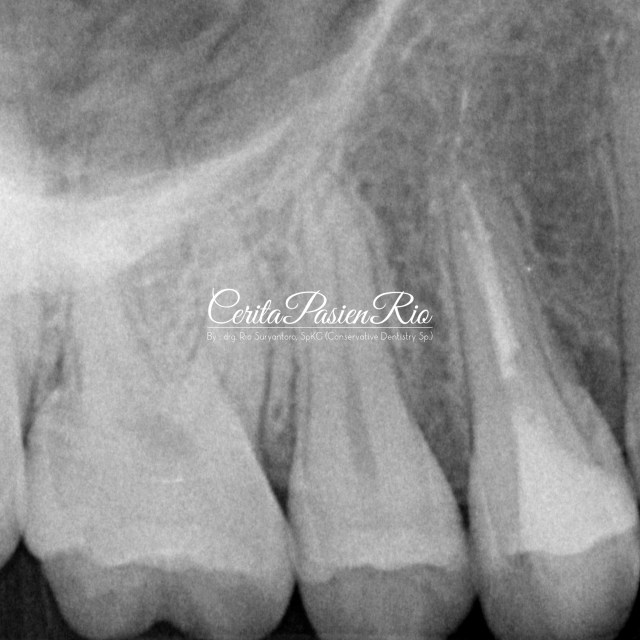

lalu, saya memulai perawatan endodontik pada gigi tersebut. dimulai dari preparasi akses sampai dengan pengisian saluran akar. Preparasi saluran akar pada gigi ini saya lakukan menggunakan ProtaperNext (dentsply), irrigasi menggunakan Natrium Hipoklorit (NaOCl) 5,24%.

gambar 5. setelah di preparasi akses, tampak garis crack di bagian oklusal bergerak sampai ke kamar pulpa

gambar 6. setelah di preparasi akses, tampak garis crack di bagian oklusal bergerak sampai ke kamar pulpa.